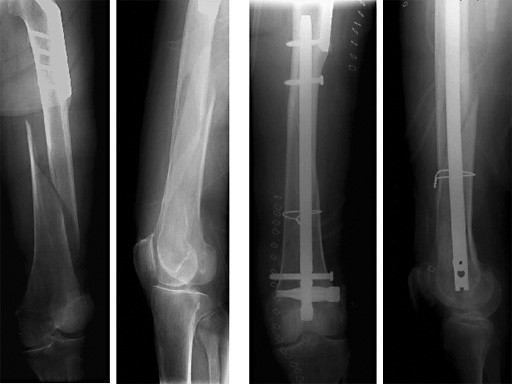

Female, 88 years

Indications include extra-articular metaphyseal distal femoral fractures (32-A1 to C3) and supracondylar fractures and simple articular fractures (33-A1 to A3 and 33-C1 to C3.1).

The Spiral Blade enables significantly more stable distal interlocking than with conventional locking bolts due to the large load-bearing surface. It reduces cancellous bone compaction and lowers the risk of nail protrusion into the knee joint. The nail diameters are 9.0 and 10.0 mm for solid nails and 12.0 mm for cannulated nails.